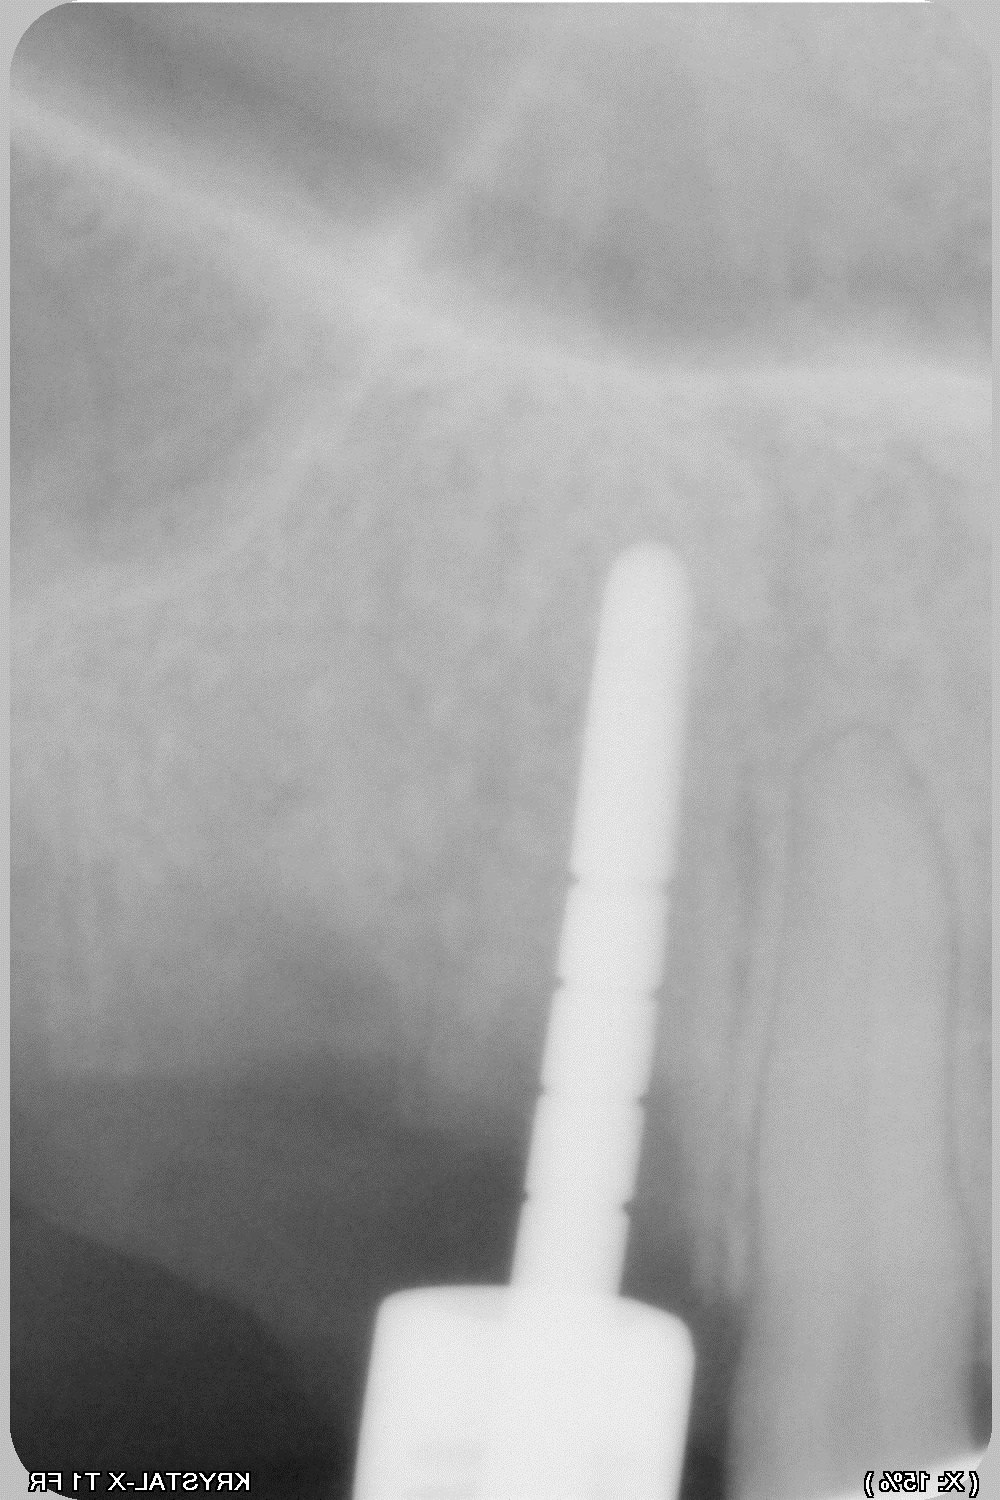

017 yxu8oi - Eugenol

018 ujs3dh - Eugenol

donc lame n°15 neuve et on grattouille... pour dégager la lame 11.

une petite erreur, de plus en pensant mobiliser 11 avec un spreader...lame 11 cassée en deux partie...

de nouveau lame 15, sonde 17, luxotome...et ça vient....mince il reste la pointe....je ne veux pas risquer de l'envoyer plus haut donc je me dis qu'elle ne gênera pas.

020 ef3xxb - Eugenol

025 vjxi28 - Eugenol

026 j2cuco - Eugenol

029 dhrqvx - Eugenol